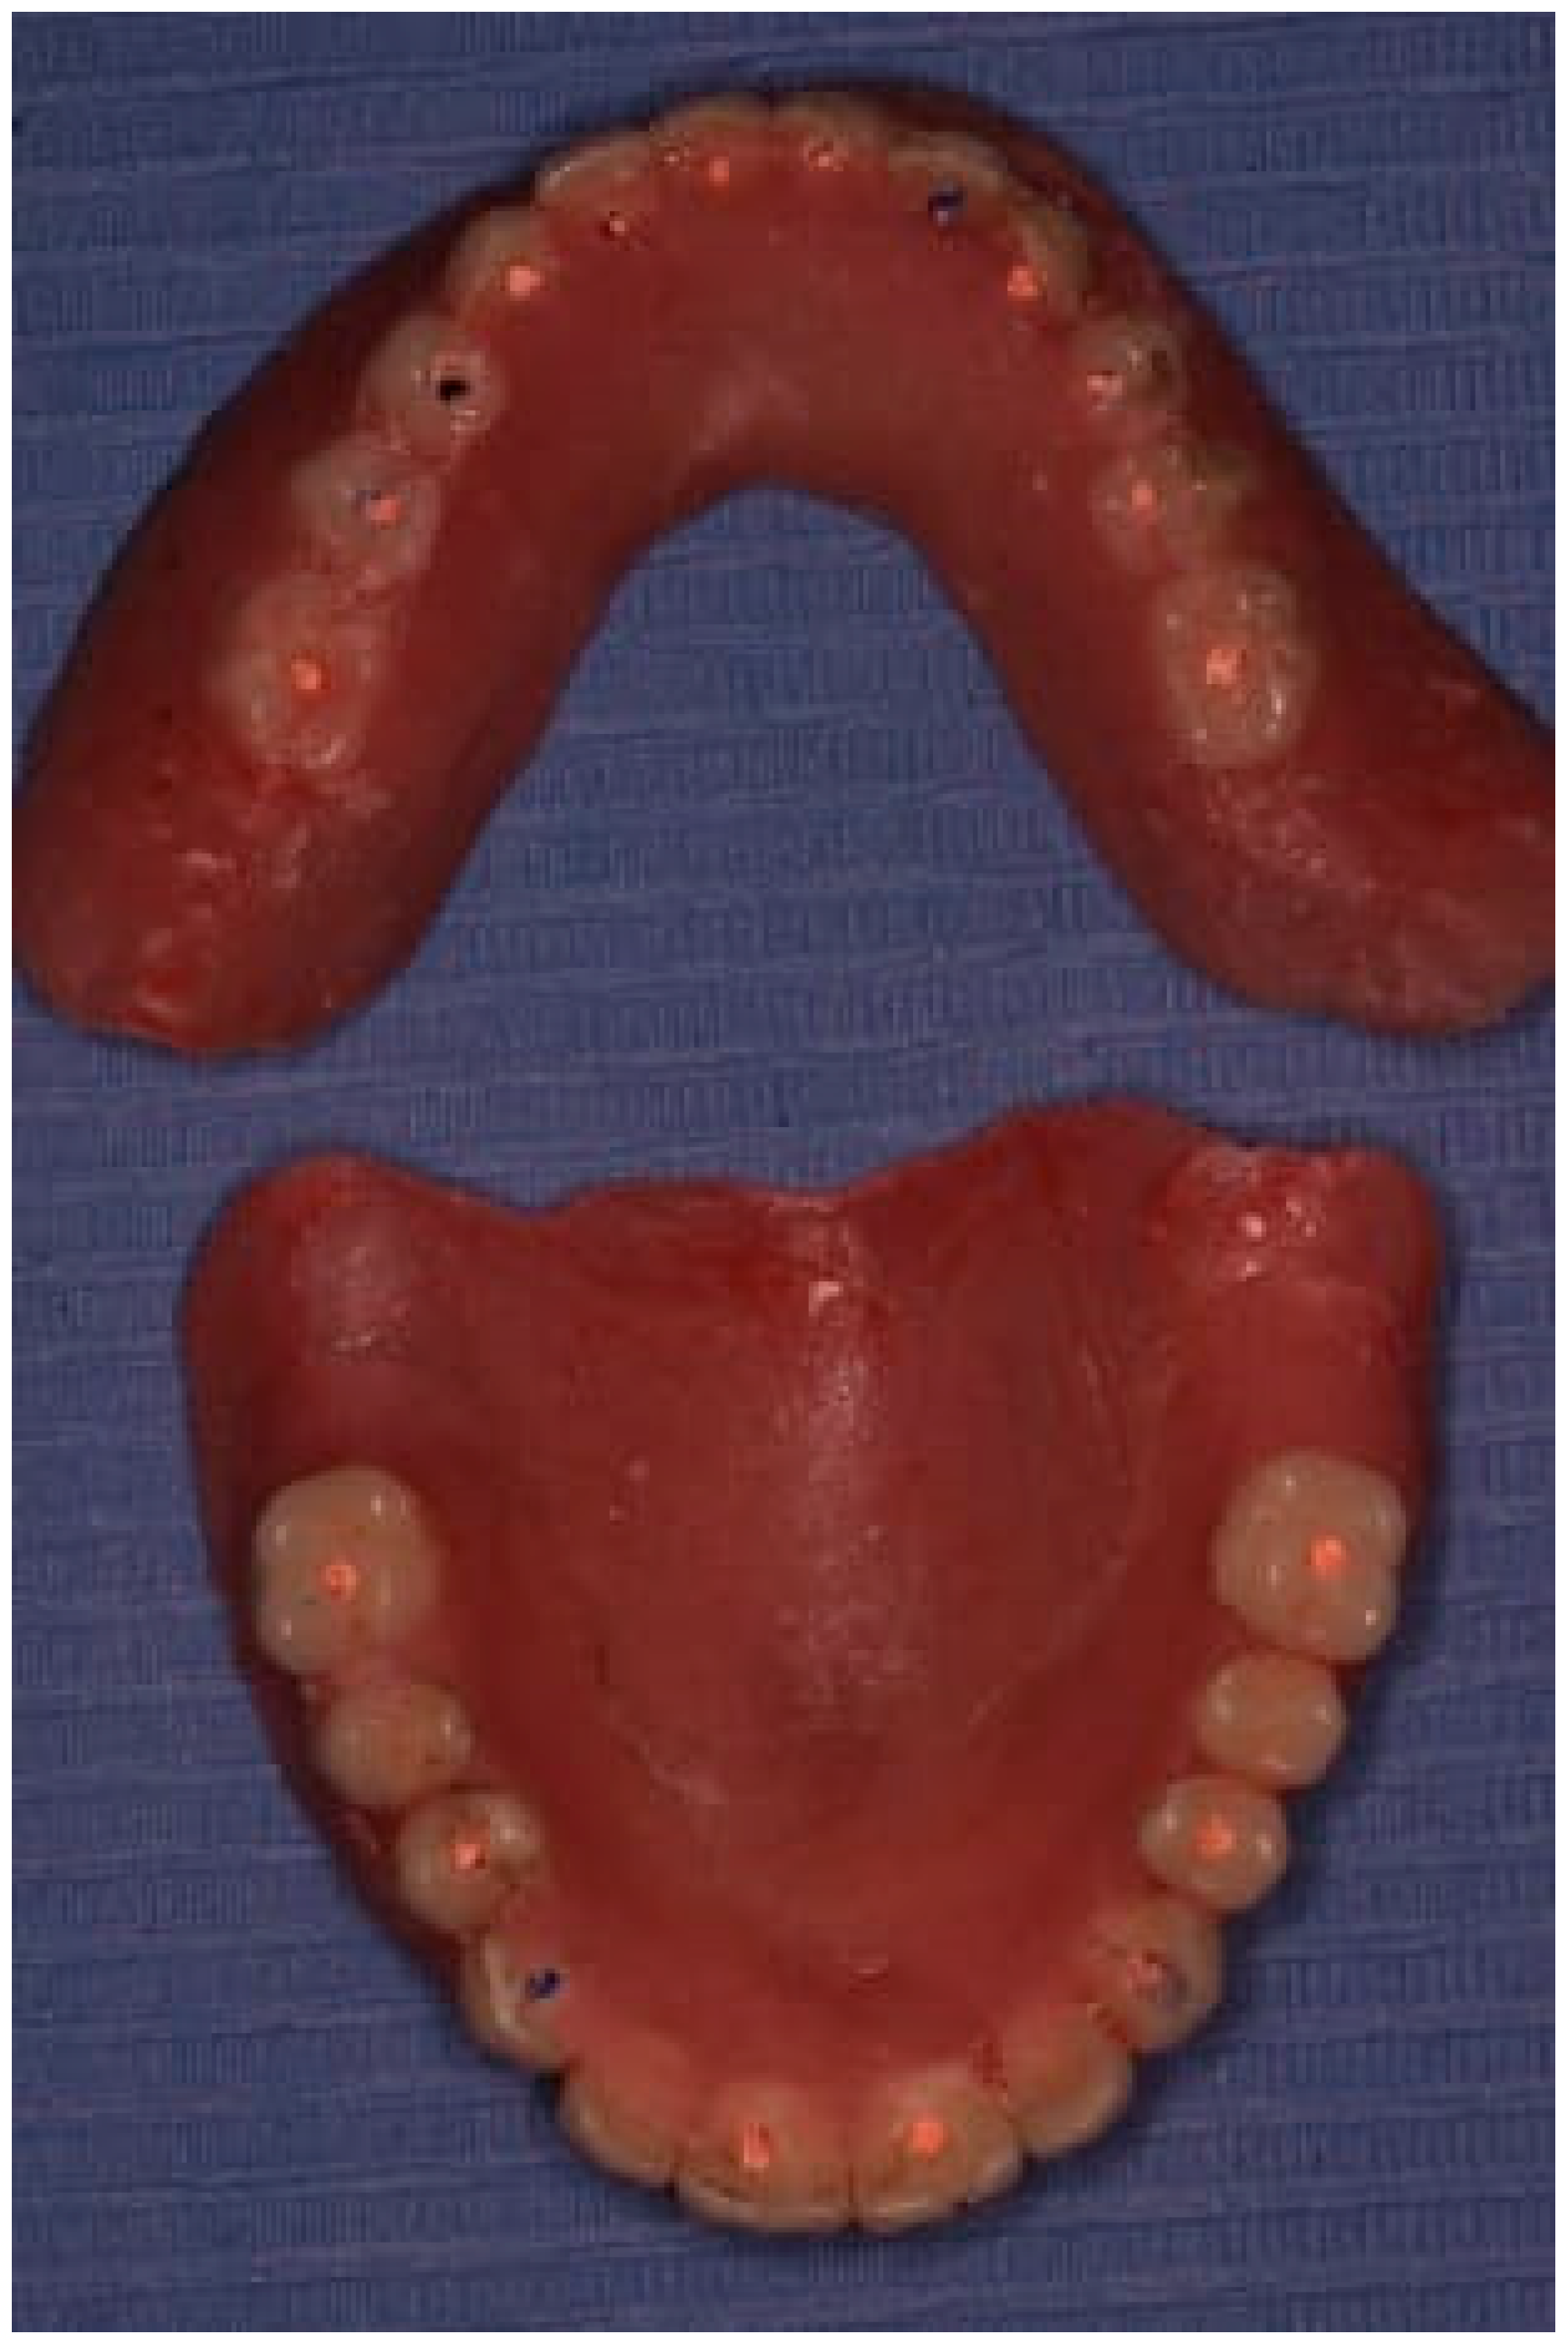

2.5. Fifth Visit

The restoration plan involved placing a bridge that connects the central incisors to the canines, along with an additional bridge spanning the first premolar to the first molar on each side of the maxillary arch. In the mandibular arch, the plan included three bridges: one connecting the lateral incisors bilaterally and another bridging the canines to the second premolars and first molars on each side (Figure 14 and Figure 15). Placing was confirmed using Panoramic radiographs obtained using the PantOs DG XP panoramic dental X-ray system (Fona S.r.l., Assago, Italy; CE 0051). The unit operates on a 230 V, 50/60 Hz input line with an 8 A fuse. Standard panoramic exposure parameters were applied (90 kVp, 10 mA, exposure time 14 s) following the manufacturer’s safety recommendations. A trained radiology technician performed all scans, and patient positioning was standardized using the built-in cephalostat support and light-beam alignment to ensure reproducibility of serial images.

Figure 14. The final prostheses.

Prosthesis 07 00145 g014

Figure 15. Panoramic X-ray showing the final prostheses (taken 21 November 2023).